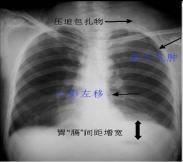

• 張力性氣胸

胸壁、肺、支氣管或食管上的創(chuàng)口呈單向活瓣,與胸膜腔相交通,吸氣時(shí)活瓣開放,空氣進(jìn)入胸膜腔,呼氣時(shí)活瓣關(guān)閉,空氣不能從胸膜腔排出,因此隨著呼吸,傷側(cè)胸膜腔內(nèi)壓力不斷增高,...